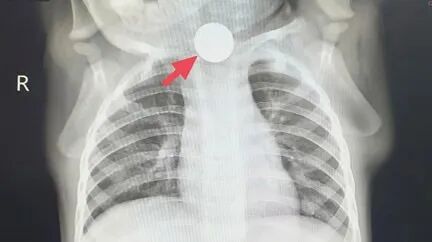

“大夫,

孩子一周没好好意思味饭了,

就靠喝奶续命,

吃了健胃药也没用啊!”

日前,

上海复旦大学附庸儿科病院消化科门诊,

一双父母抱着一岁的宝宝冬冬(假名),

满脸慌乱地乞助。